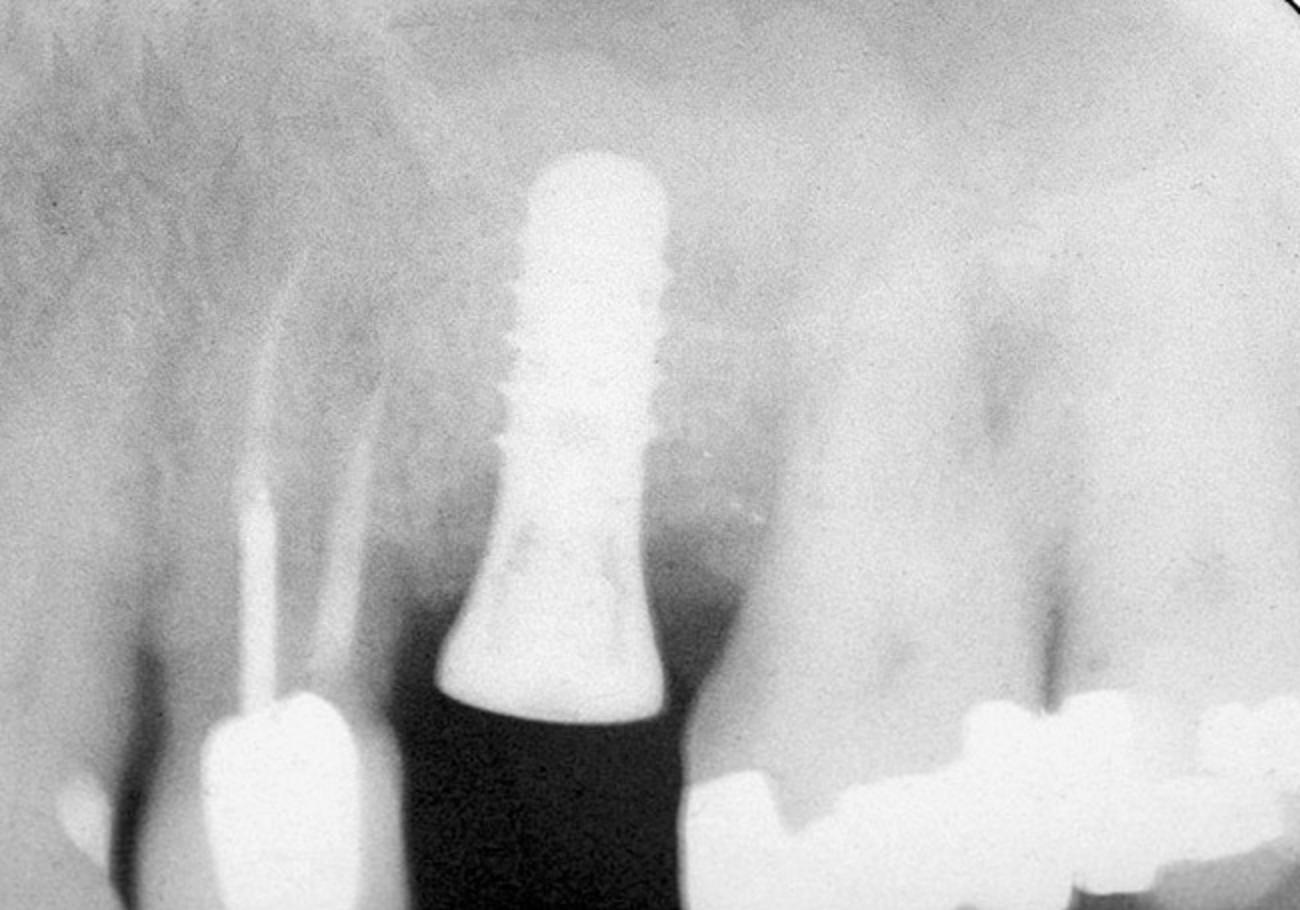

Figure 4  After infracturing the subantral wall with a 3.5-mm osteotome, bone was added and the presence of a dome was confirmed with a radiograph.

Figure 4

Figure 6  At site No. 14, a radiograph depicting the full "dome" of graft material apical to the implant.

Figure 6

Figure 7  Radiograph depicting a "flattening" of the dome that has taken place in the first year after the graft was performed. This shows consolidation of the graft and remodeling that takes place over time.

Figure 7